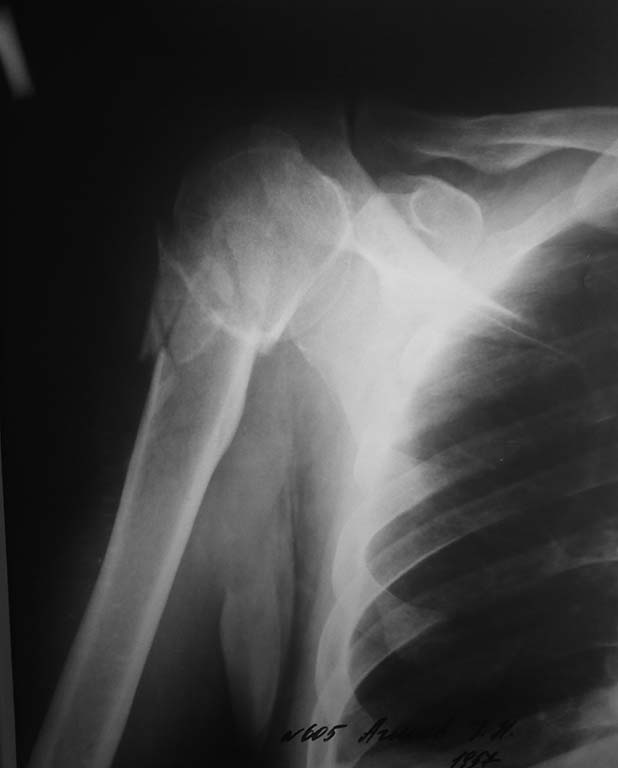

остеосинтез проксимального конца плеча

остеосинтез шейки плеча

какие методы лечения можете предлагать для данного перелома?

доступ при переломе шейки плеча?